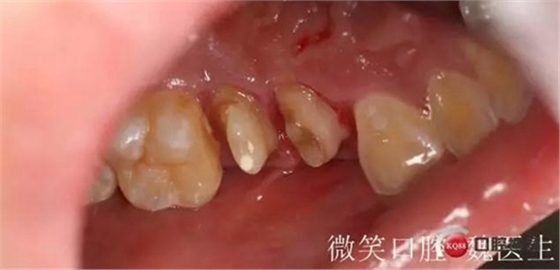

圖片可看出五號(hào)牙已經(jīng)是殘根而且多年未修復(fù)還向遠(yuǎn)中 移位和六號(hào)牙貼在一起

4號(hào)牙也是大面積缺損